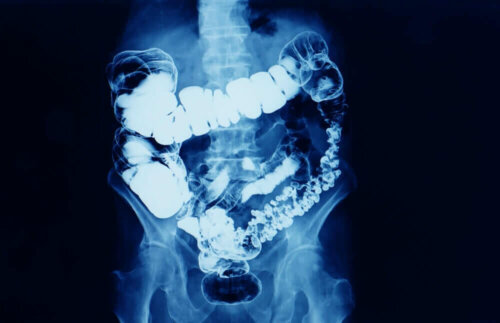

Glycerol is the active ingredient in glycerin suppositories. It’s a substance that exerts its laxative action when administered rectally. This effect is achieved because when the suppositories are administered, the stool softens and produces a mild local irritating effect, stimulating intestinal peristalsis.

- Local irritant effect on the rectal mucosa: the irritant effect doesn’t affect the intestinal walls. It causes the contraction of the rectum promoting the expulsion of stool.

- Osmotic effect: glycerol absorbs water and this, together with its lubricating properties, softens the stool and facilitates its expulsion.